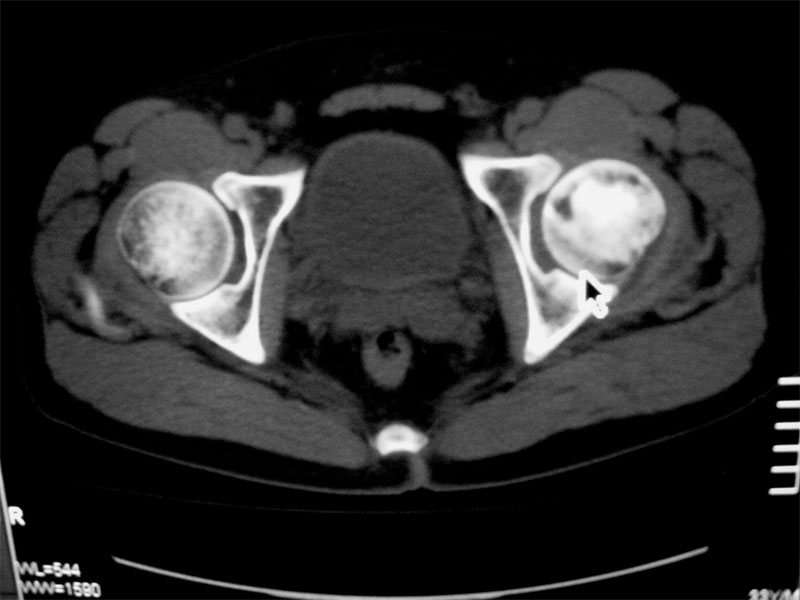

标题: CT16604:男32岁,左髋关节处疼痛月余 [打印本页]

标题: CT16604:男32岁,左髋关节处疼痛月余

左股骨头缺血性坏死

双侧股骨头坏死

考虑左股骨头缺血性坏死;建议必要时行mri检查。

考虑左股骨头缺血性坏死;建议必要时行mri检查。右侧拍平片

左侧髋关节少量积液.上传骨窗

双侧股骨头坏死!!

左侧股骨头坏死,左侧髋关节少量积液

考虑左侧股骨头坏死。

考虑左股骨头缺血性坏死;右股骨上段良性骨肿瘤,考虑成软骨细胞瘤可能。建议上传骨窗。